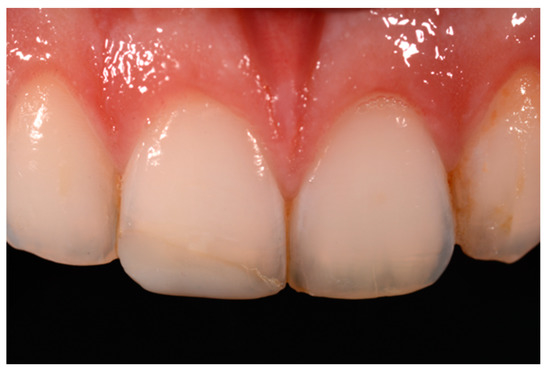

A healthy 10-year boy presented to the dental office after traumatic accident during sport activity. Upper central incisor presented horizontal fracture with no pulp exposure (Figure 1 and Figure 2). Tooth fragment was not retrieved after the traumatic accident. The tooth responded positively to pulp tests (cold and electrical). In order to manage sensitivity and protect the tooth before the restoration appointment, after rubber dam placement, a universal adhesive (Clearfil Universal Bond Quick, Kuraray Noritake Dental, Tokyo, Japan) was applied in self-etch mode followed by a little layer (approximatively 0.5 mm) of flowable composite (Clearfil Majesty ES Flow, A2, Kuraray Noritake Dental, Tokyo, Japan). A silicone impression (Imprint, 3M ESPE, St. Paul, MN, USA) was therefore taken in order to develop a wax-up (Figure 3) and a palatal silicone index (Elite HD+, Zhermack, Badia Polesine, Italy).

Figure 1.

Initial clinical situation. Reprinted from Restauri diretti nei settori anteriori, G. Paolone, S. Scolavino, © 2021, with permission from Quintessence Publishing Italy.